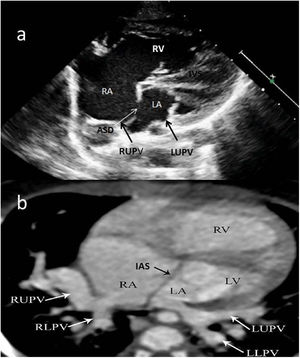

Two-year-old female patient with septum primum malposition and partial anomalous pulmonary venous return. (a) Modified 4-chamber view on echocardiographic examination; (b) computed tomography images in axial view. ASD: atrial septal defect; IAS; interatrial septum; IVS: interventricular septum; LA; left atrium; LLPV: left lower pulmonary vein; LUPV; left upper pulmonary vein; LV: left ventricle; RA; right atrium; RLPV: right lower pulmonary vein; RUPV: right upper pulmonary vein; RV: right ventricle.